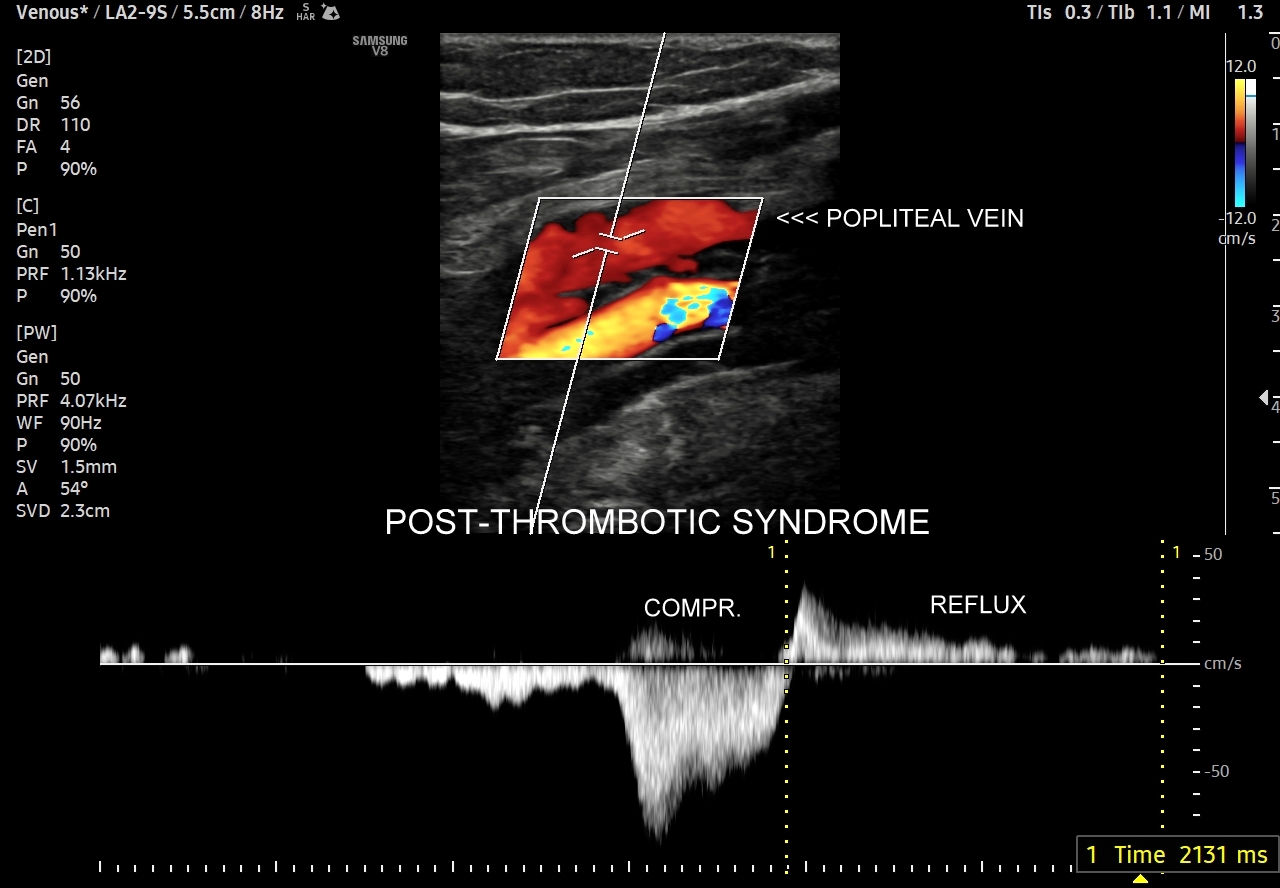

42. Patologie żył kończyn dolnych, w tym niewydolność żył powierzchownych i głębokich, żylaki, zakrzepica żył powierzchownych, zakrzepica żył głębokich, zespół pozakrzepowy.

Dzień żylny w ramach Kursu dedykowany jest dopplerowskiemu badaniu żył, w szczególności w obrębie kończyn dolnych. Otóż to właśnie w tym obszarze ujawniają się najczęściej choroby układu żylnego takie jak zakrzepica żył głębokich, zakrzepica żył powierzchownych, niewydolność żył powierzchownych i żylaki podudzi, niewydolność żył głębokich i zespół pozakrzepowy, które to badający lekarz powinien umieć rozpoznać. W trakcie interdyscyplinarnego Kurs USG Doppler Cedum ® omawiane są również hemodynamika krążenia żylnego w fizjologii i w stanach patologicznych; cele diagnostyczne, w tym planowanie zabiegów angiochirurgicznych i endowaskularnych w obrębie żył; a także nauczane są techniki funkcjonalnego badania żył kończyn dolnych i żył miednicy. Kurs obejmuje także tematykę dotycząca żyły głównej dolnej i jej brzusznych dopływów, żył szyjnych oraz żył kończyn górnych.